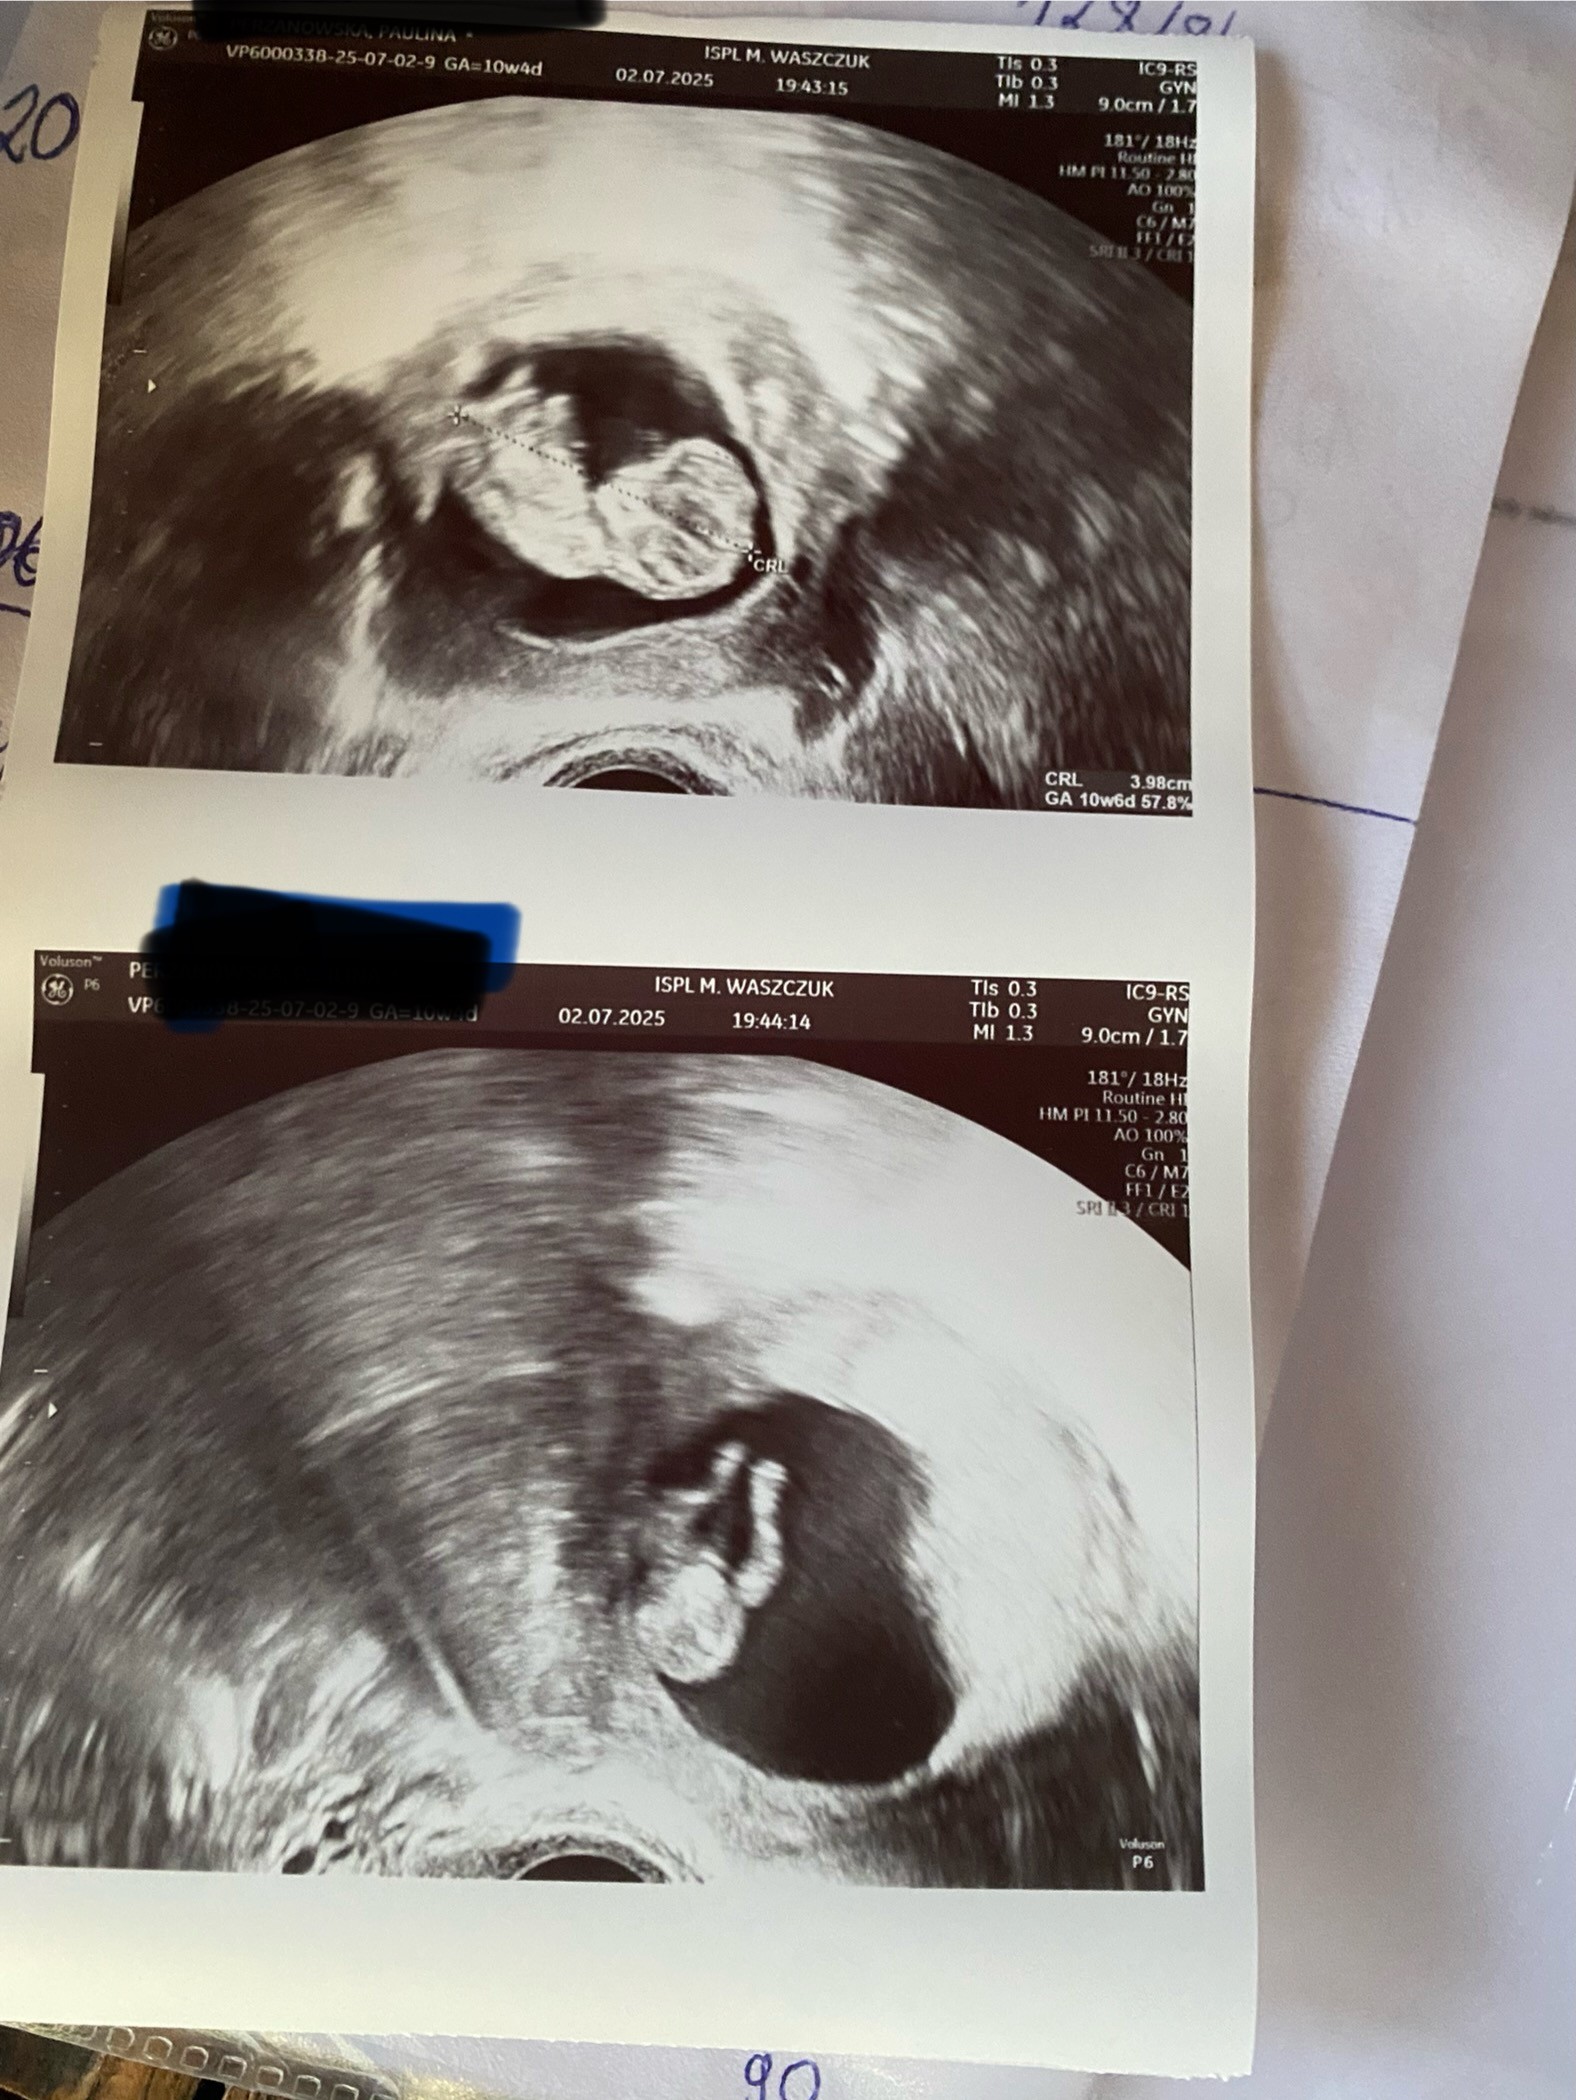

Moja mała wielka miłość 🥰 dzisiaj byliśmy na usg wszystko jest idealnie jest 2 dni starszy z USG 🥰🥰ale wyszła mi cukrzyca ciążowa 😩i w środę mam Diabetologa 🤦‍♀️Wszystko zrobię aby tylko insuliny nie było i aby z maluchem było wszystko ok 🥰🥰🥰Córeczka moja to kazała dać zdjęcie w ramkę i postawiła na biurku 🥰🥰🥰aby codziennie brata widzieć to takie wzruszające

• IMG_5453.jpeg

IMG_5453.jpeg

581,4 KB · Wyświetleń: 84